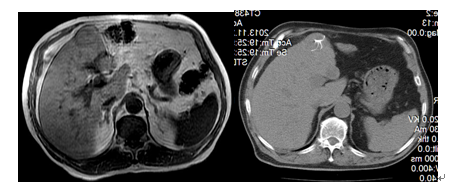

(二)、患者、男、68岁,2013年11月发现肝癌术后5年复发,因患者肾功能不全,不适宜外科手术及血管内介入治疗,在我院行CT引导下射频消融治疗,术后结合中药治疗目前病情稳定。